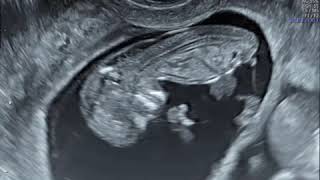

Nuchal Translucency Scan - First Trimester

Nuchal Translucency Ultrasound 12 Weeks Pregnant

How to Measure Nuchal Translucency (NT) On Ultrasound | First Trimester NT Screening | Fetal USG